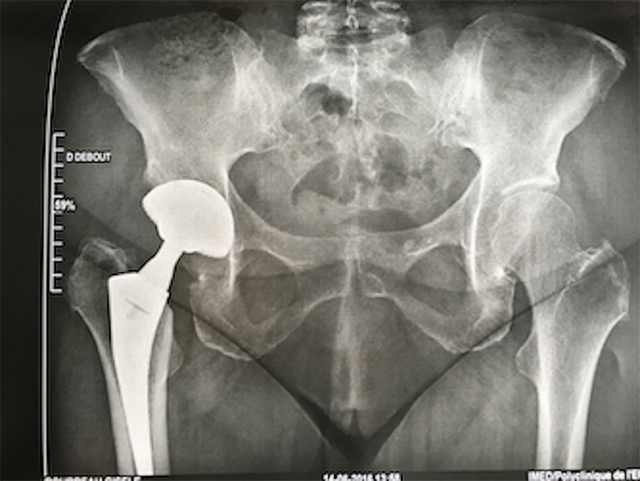

Hemiarthroplasty –үеийг хагас солих

Хугарал засах мэс засал image8

УНТЭ-т хийгдсэн мэс заслын зураг